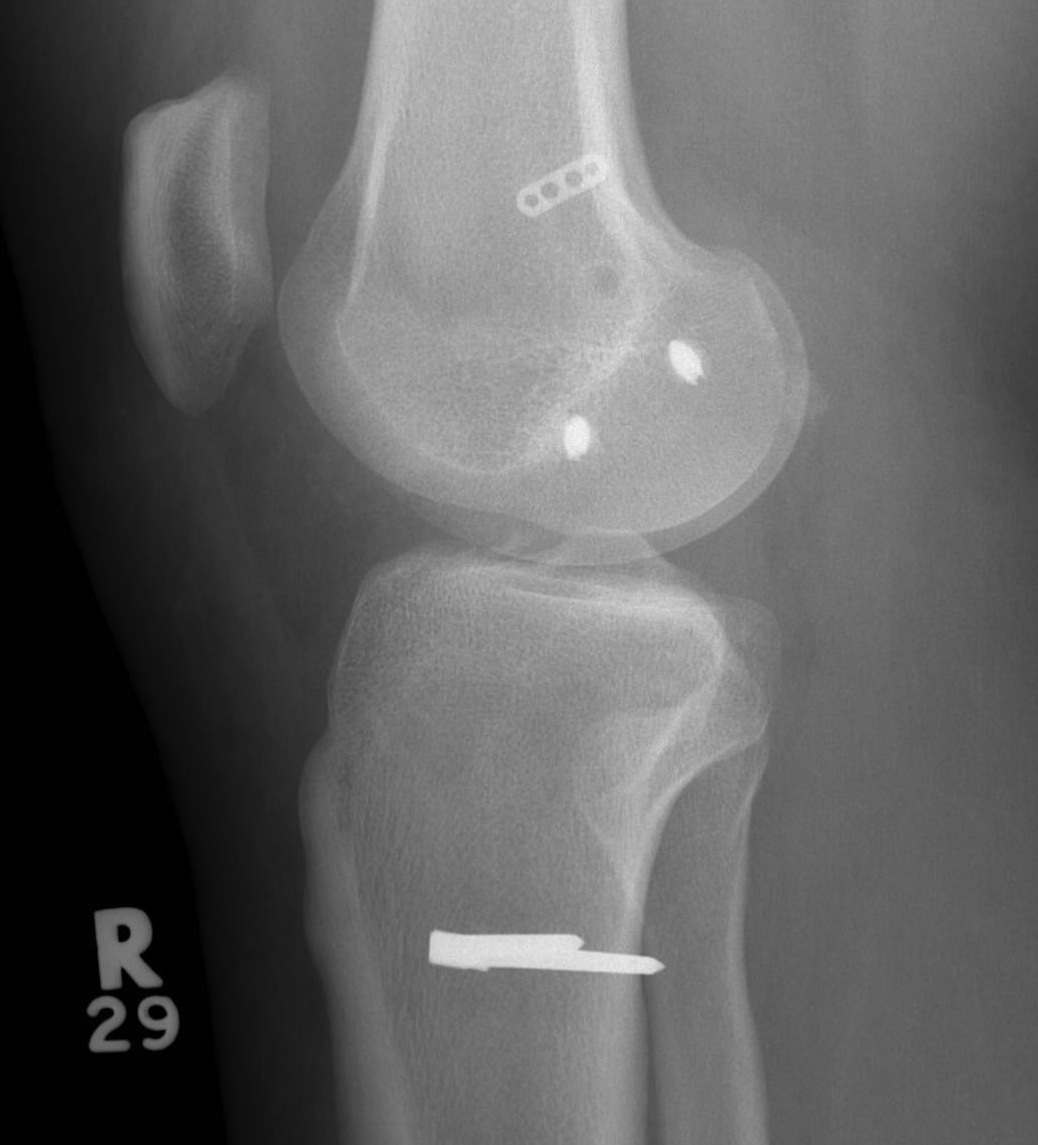

Bony MCL Avulsion

Elevate VMO and repair with staples or screw

Advancement of proximal MCL / POL with screw, and imbrication / tightening of POL

Tightening of proximal MCL / POL with sutures

Advancement of femoral MCL and staple / suture anchor fixation

Femoral attachment

- 4 mm proximal and posterior to medial epicondyle

- image intensifier: intersection of the posterior femoral condyle with Blumensaat's line

- 40o anterior to avoid notch

- 40o proximal to avoid PCL tunnel

Tibial attachment

- 6 cm from joint line

- just posterior to pes attachment